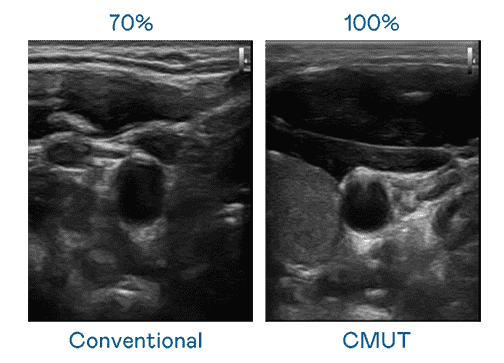

CMUT 技术是一种用电容式微机电元件来产生超音波讯号的技术。。。。与传统 PZT 压电式技术相比,,,,CMUT 频宽增加 30%,,,更宽频的超音波讯号让影像解析度大幅提升,,是实现高影像品质医疗超音波扫描、、、、促进精准医疗发展的关键技术。。。

超音波影像的解析度高低,,,首先取决于探头能发出的讯号频宽。。z6mg·人生就是博 CMUT 可提供高清晰的超音波讯号,,提供高频宽、、、、高灵敏度、、、影像纹理细节更高的超音波影像,,,协助医护人员缩短影像判读时间及利用精准的医疗影像进行诊断。。。